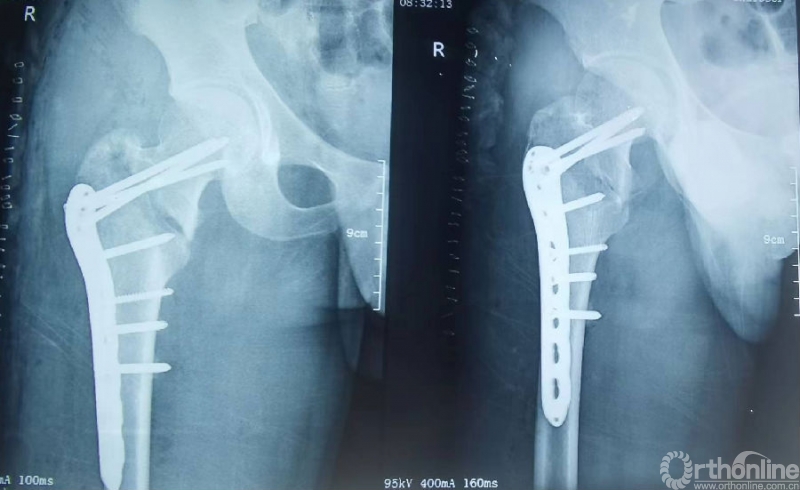

影像学资料

诊断:1、股骨颈骨折(Garden III);2、帕金森病

初次治疗:闭合复位空心螺钉内固定

术后影像资料(2022.3.2)

术后2个月(2022.5.27)